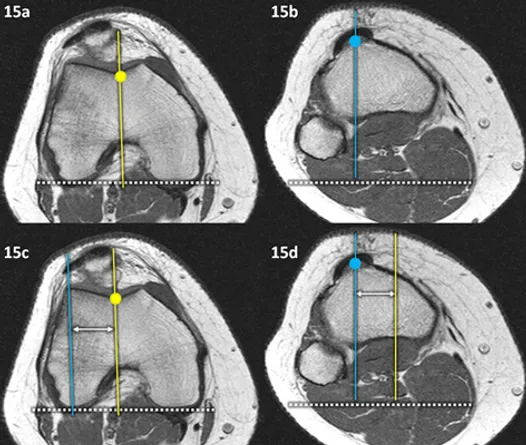

Figuras 14 e 15 (a-d): Imagens consecutivas no plano transversal de TC (14 a-d) e RM na ponderação T1 (15a-d) mostrando como medir a distância TA-GT (TT_GT) propagando as retas. Após a definição dos pontos GT (pontos amarelos) e TA ou TT (pontos azuis) é traçada a linha bicondiliana posterior (linha tracejada branca) que posteriormente é copiada para as imagens no plano da tuberosidade da tíbia (figuras 14 e 15b e 15d). São então traçadas as linhas perpendiculares à linha bicondiliana posterior, uma passando pelo fundo da tróclea (linhas amarelas) e outra passando pelo centro do ligamento patelar na sua inserção na tuberosidade da tíbia (linhas azuis). Essas linhas são então copiadas para que possa ser medida a distância TA-GT (setas duplas brancas), podendo tanto copiarmos a linha azul que passa pelo ponto TA ou TT para a imagem da tróclea, como nas figuras 14 e 15c, ou copiarmos a linha amarela que passa pelo ponto GT para a imagem da tuberosidade da tíbia, como nas figuras 14 e 15d.

A escola Lyonesa utiliza a estratégia “le menu à la carte”, onde cada alteração morfológica é corrigida por uma técnica cirúrgica específica. As técnicas cirúrgicas mais utilizadas são as reconstruções ligamentares e a transferência da tuberosidade tibial nos casos em que ela está mais lateralizada que o habitual, procedimentos que foram realizados nesta paciente alguns meses depois da solicitação da tomografia computadorizada com normalização da distância TA-GT (figuras 16 e 17):